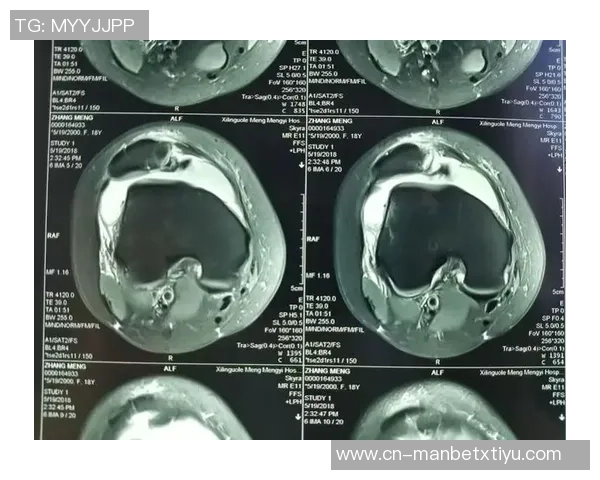

幸运的是,通过X光结果显示并未发现明显异常,这意味着目前没有骨折或严重损害的迹象。然而,这并不代表他完全没有危险,因为软组织损伤如韧带扭伤等问题仍然需要进一步确认。因此,医生建议进行MRI检查以获得更详细的信息。

MRI(磁共振成像)是一种无创性的高分辨率影像学技术,可以清楚地显示软组织结构,因此对于评估肌肉、韧带和其他组织的损伤尤为重要。这也是为什么医生会选择第二次检查,以确保全面了解约维奇的实际情况。